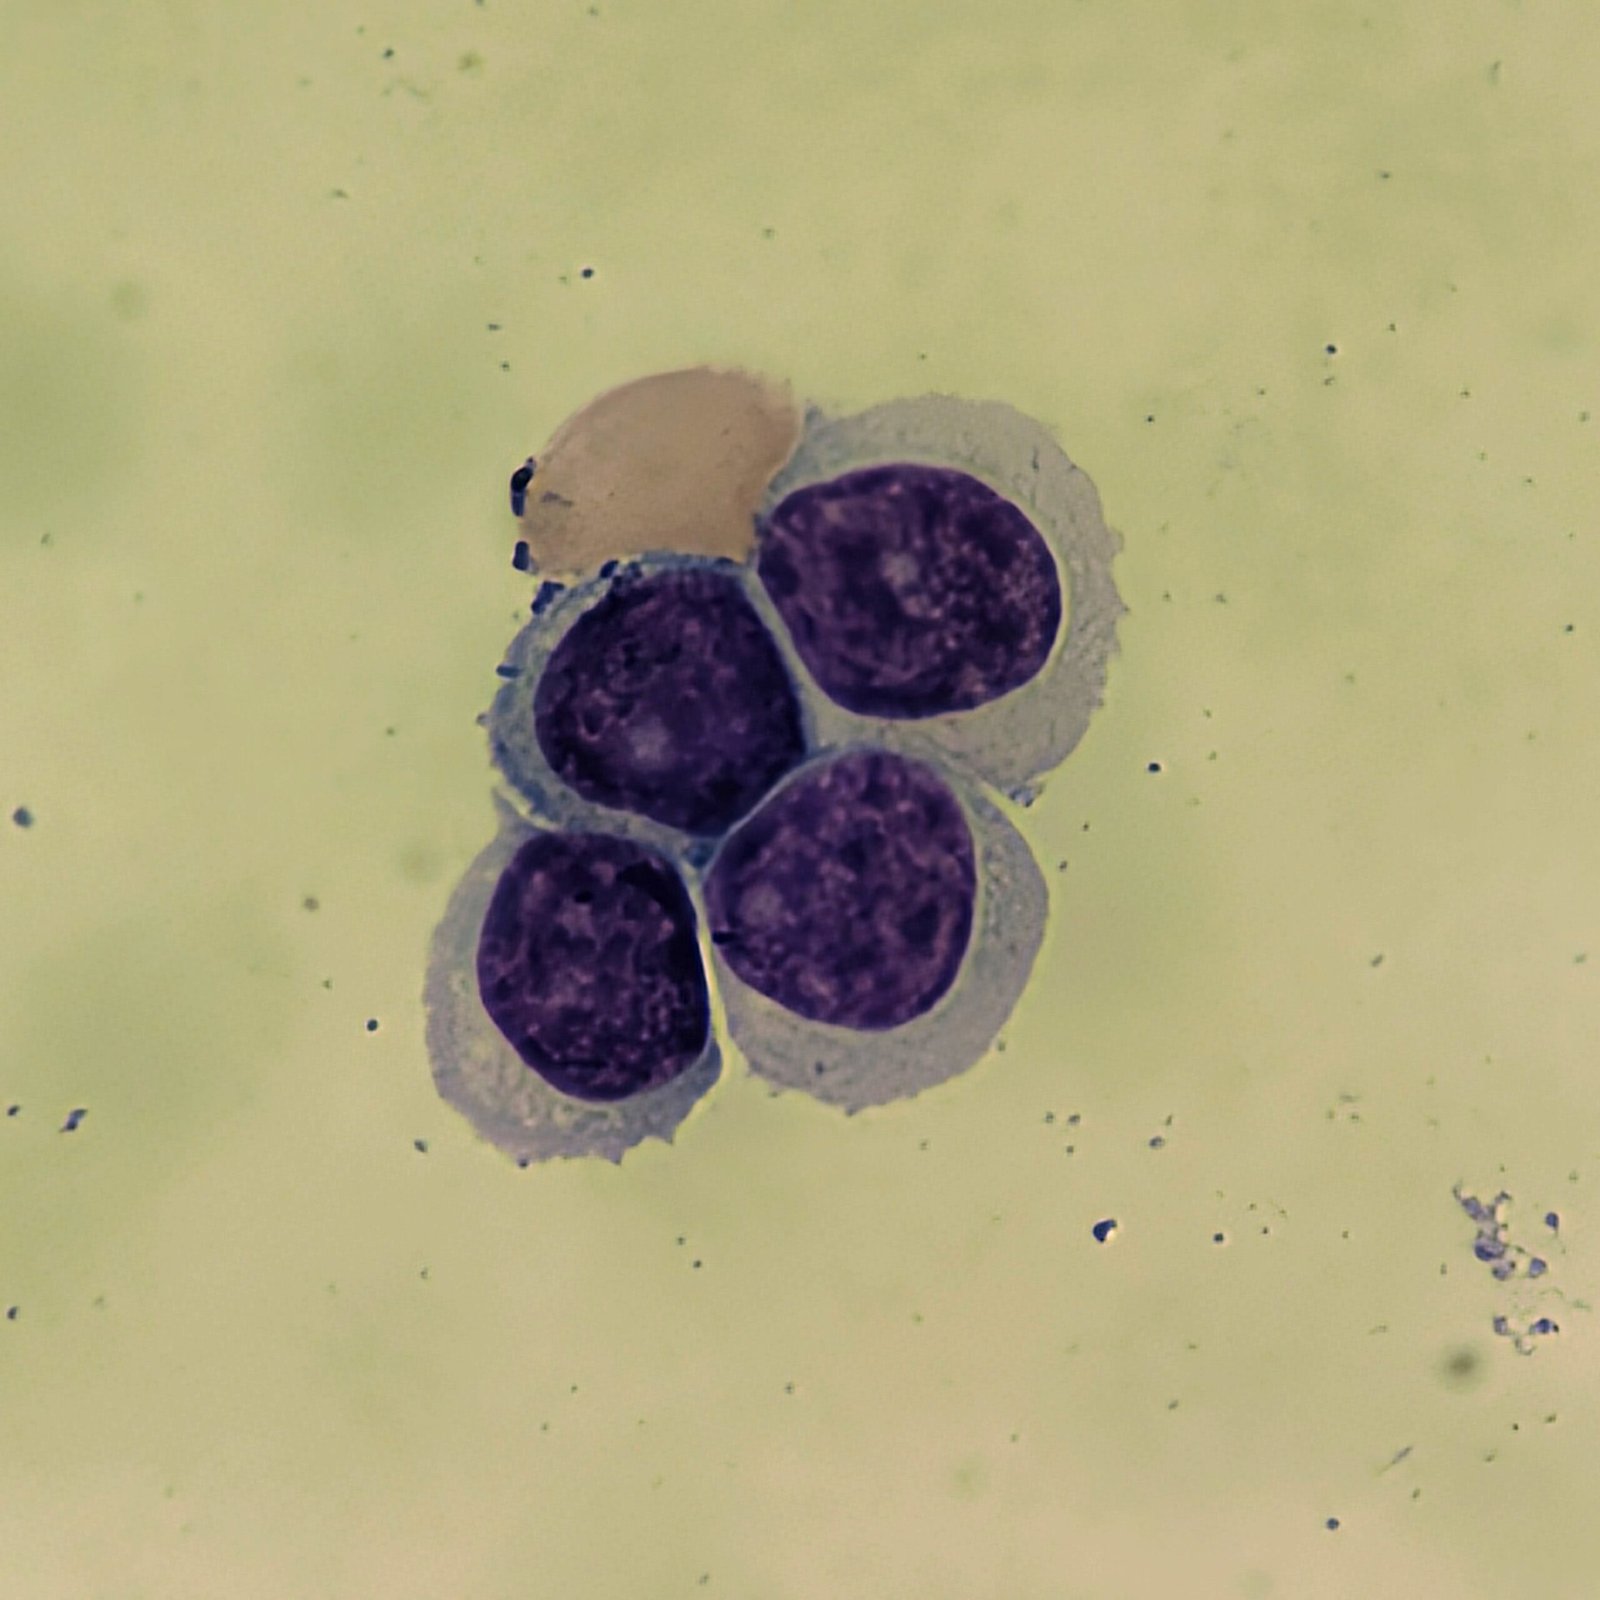

Mesothelial cells are described as having a “fried egg” appearance. They have a round to oval nucleus with smooth borders and evenly distributed chromatin. Nucleloli are usually present. Mesothelial cells may also be multinucleated.

Cells may be seen in clumps, but “windows” between cells still allows for individual counting.

Both malignant cells and mesothelial cells can clump together. However, malignant cells will not have the windows between cells.